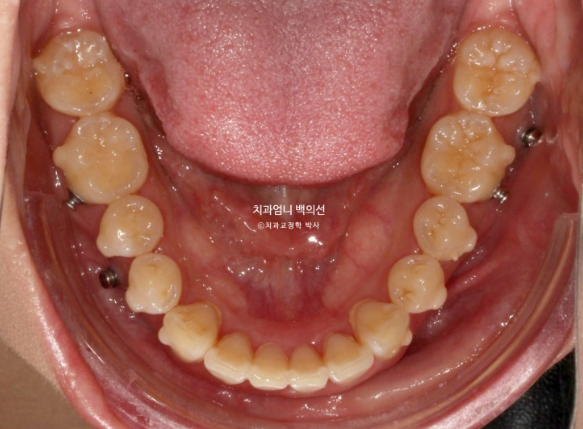

위 작은어금니 2개 발치 아래는 매복사랑니 발치 후 작은 어금니 발치 없이 미니스크류를 심고 후방이동 하는 계획입니다.

교정장치는 인비절라인이며 23년 3월에 장치를 끼기 시작했습니다.

치료시작 8개월차 발치공간으로 앞니가 이동하면서 원래 깊었던 앞니 교합이 점점 더 깊어지는 것이 관찰됩니다.

이 부분 해결을 위해서는 원래 계획에 없었지만 앞니에 미니스크류 2개를 추가로 식립하고 고무줄을 걸기 시작합니다.

23년 3월부터 24년 5월까지 1년 2개월간 52개의 장치를 낀 후 재제작 당시의 모습 보여드리겠습니다.

과개교합은 잘 개선이 되었습니다.

미니스크류와 고무줄의 조합은 인비절라인 발치교정이 성공으로 가는 노하우 입니다.

처음부터 계획하지는 않지만 적절하게 중간에 개입하여 부적절한 치아이동을 컨트롤 하는 중요한 도구입니다.

발치공간이 아직 남아있고 앞니 각도의 개선이 더 필요합니다.

아래 어금니들은 사랑니 공간으로 잘 이동했습니다.